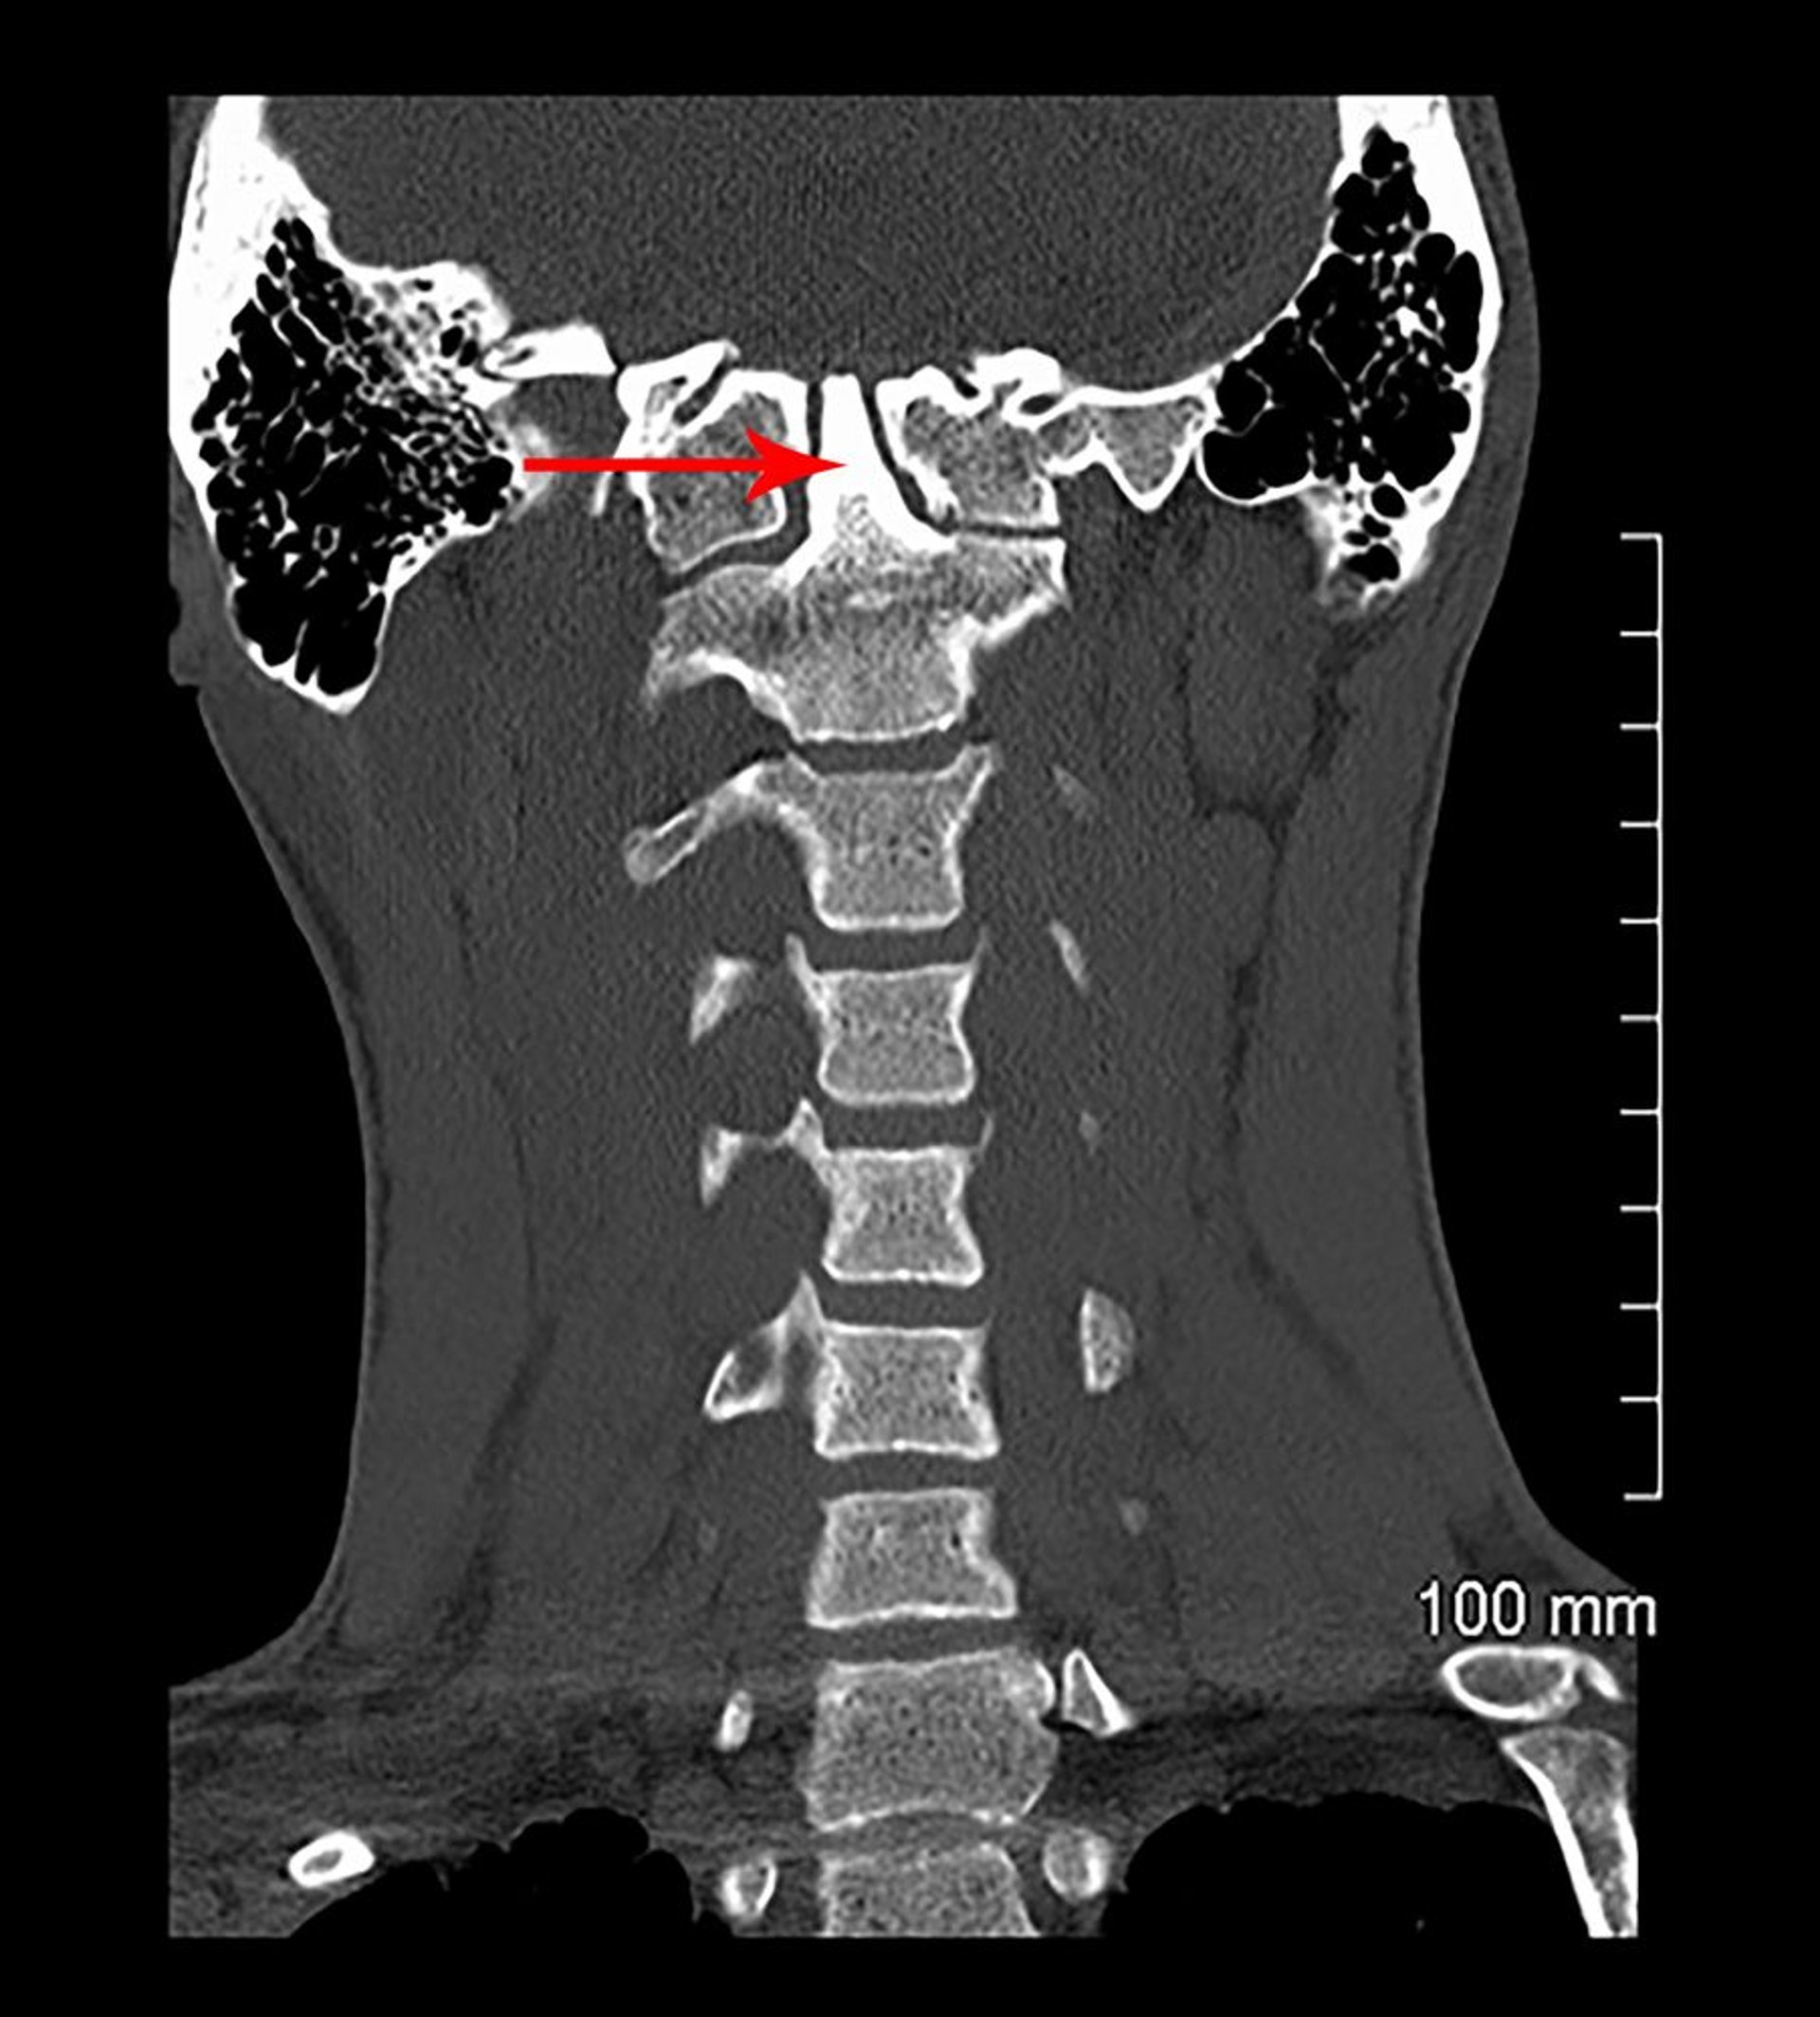

Invagination basilaire et assimilation congénitale (TDM)

Dans cette vue coronale d'une TDM, C1 est fusionné à la base du crâne (congénitalement). Le processus odontoïde (indiqué par une flèche) s'étend dans la base du crâne (invagination basilaire).